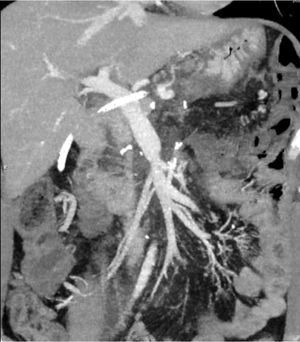

Técnica quirúrgica (vídeo cirugía)El uso de shunt íleo-cava transitorio se indicó en un paciente de 45 años afecto de adenocarcinoma de páncreas localmente avanzado que condicionaba una severa colateralidad venosa, con mutación BRCA2; tras recibir 11 ciclos de neoadyuvancia con esquema FOLFIRINOX, con buena tolerancia. Finalizado este, se realizó estudio mediante tomografía computarizada (TC) toraco-abdominal, PET/TC, y resonancia magnética nuclear (RNM), descartando afectación a distancia. Tras presentar el caso en comité multidisciplinario se planificó la intervención con ayuda de estudio 3D13 (figs. 1, 2, 3 y 4)(https://www.cellams.com). En el estudio preoperatorio se evidenció lesión pancreática con afectación del confluente venoso EMP con extensión hasta la confluencia de dos venas ileales (Vil1 y Vil2) y yeyunal (VYy), y contacto con la arteria mesentérica superior (AMS). La afectación de toda la extensión de la vena mesentérica superior (VMS) comportaba la imposibilidad de la anastomosis con seguridad.

Estudio 3D preoperatorio13. Se evidencia la oclusión del eje esplenoportomesentérico y abutment de la arteria mesentérica superior por el tumor.

SMA: arteria mesentérica superior; CHA: arteria hepática común; PHA: arteria hepática propia; GDA: arteria gastroduodenal; SA: arteria esplénica; PV: vena porta; SV: vena esplénica; VIL: vena ileal; VIL1: vena ileal tributaria 1; VIL2: vena ileal tributaria 2; VYY: vena yeyunal; IMV: vena mesentérica inferior; MSC: mesocolon.

En amarillo se señala el tumor pancreático.

Detalle de la vascularización venosa del estudio 3D13.